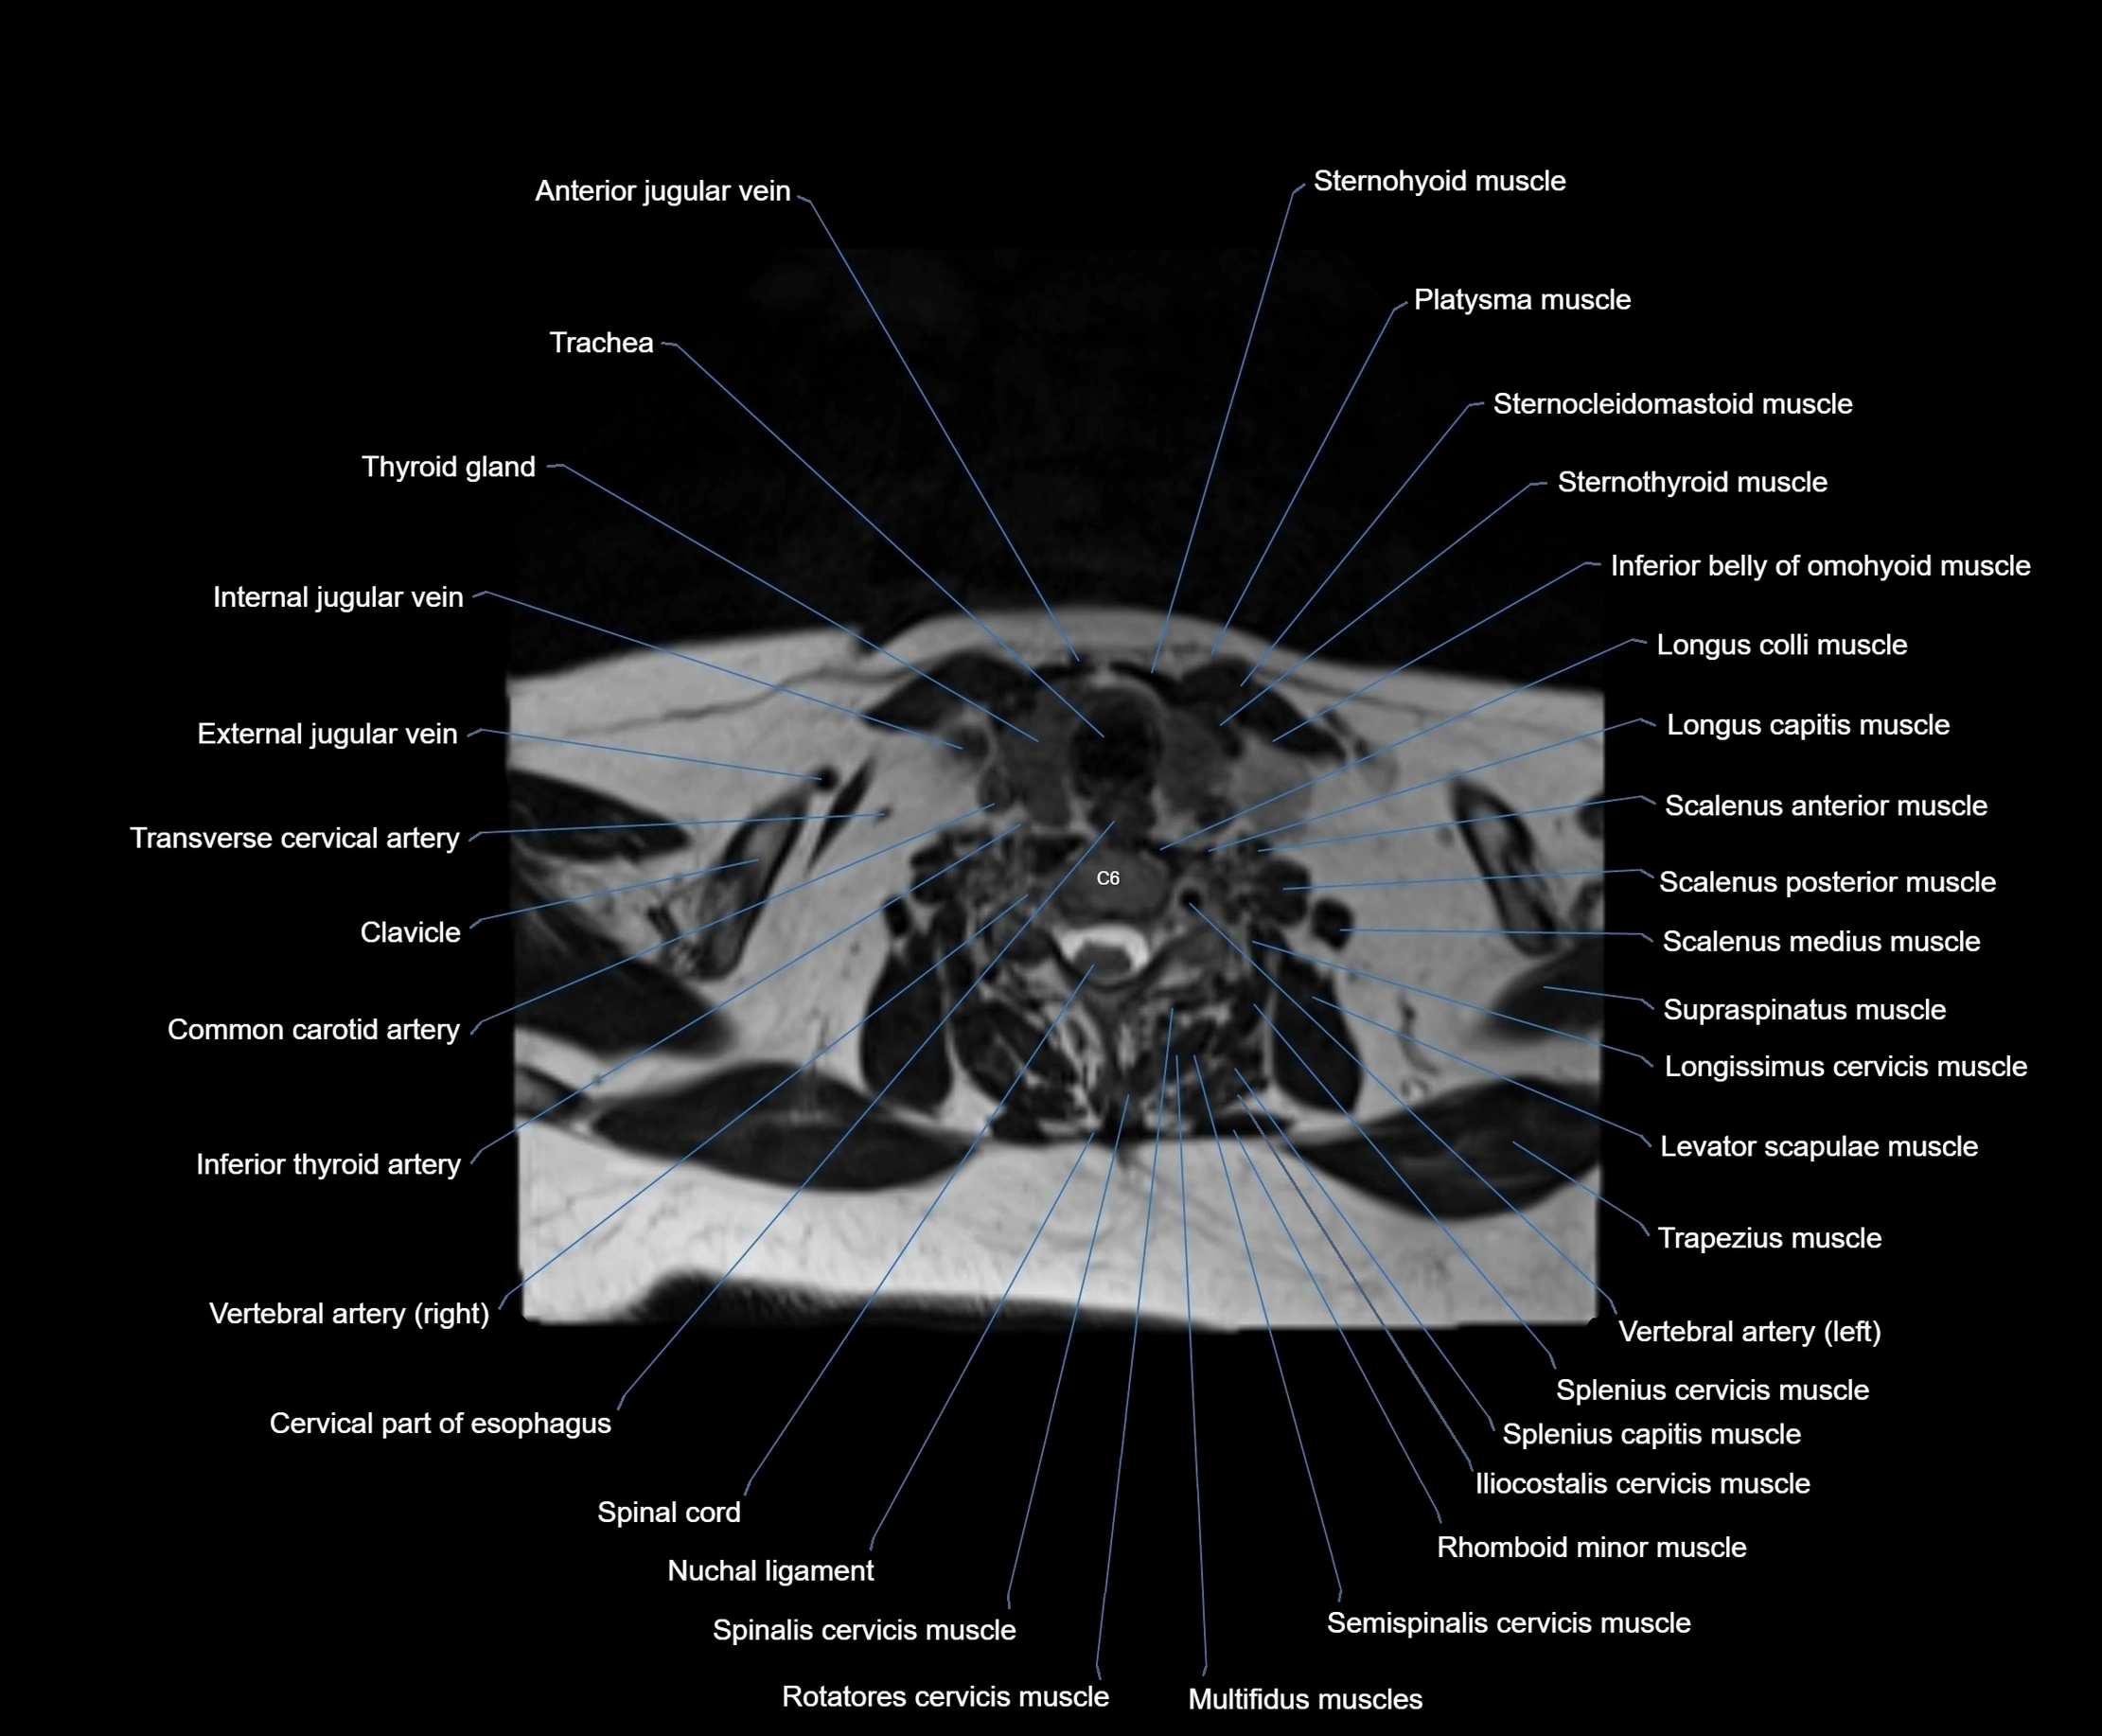

MRI images